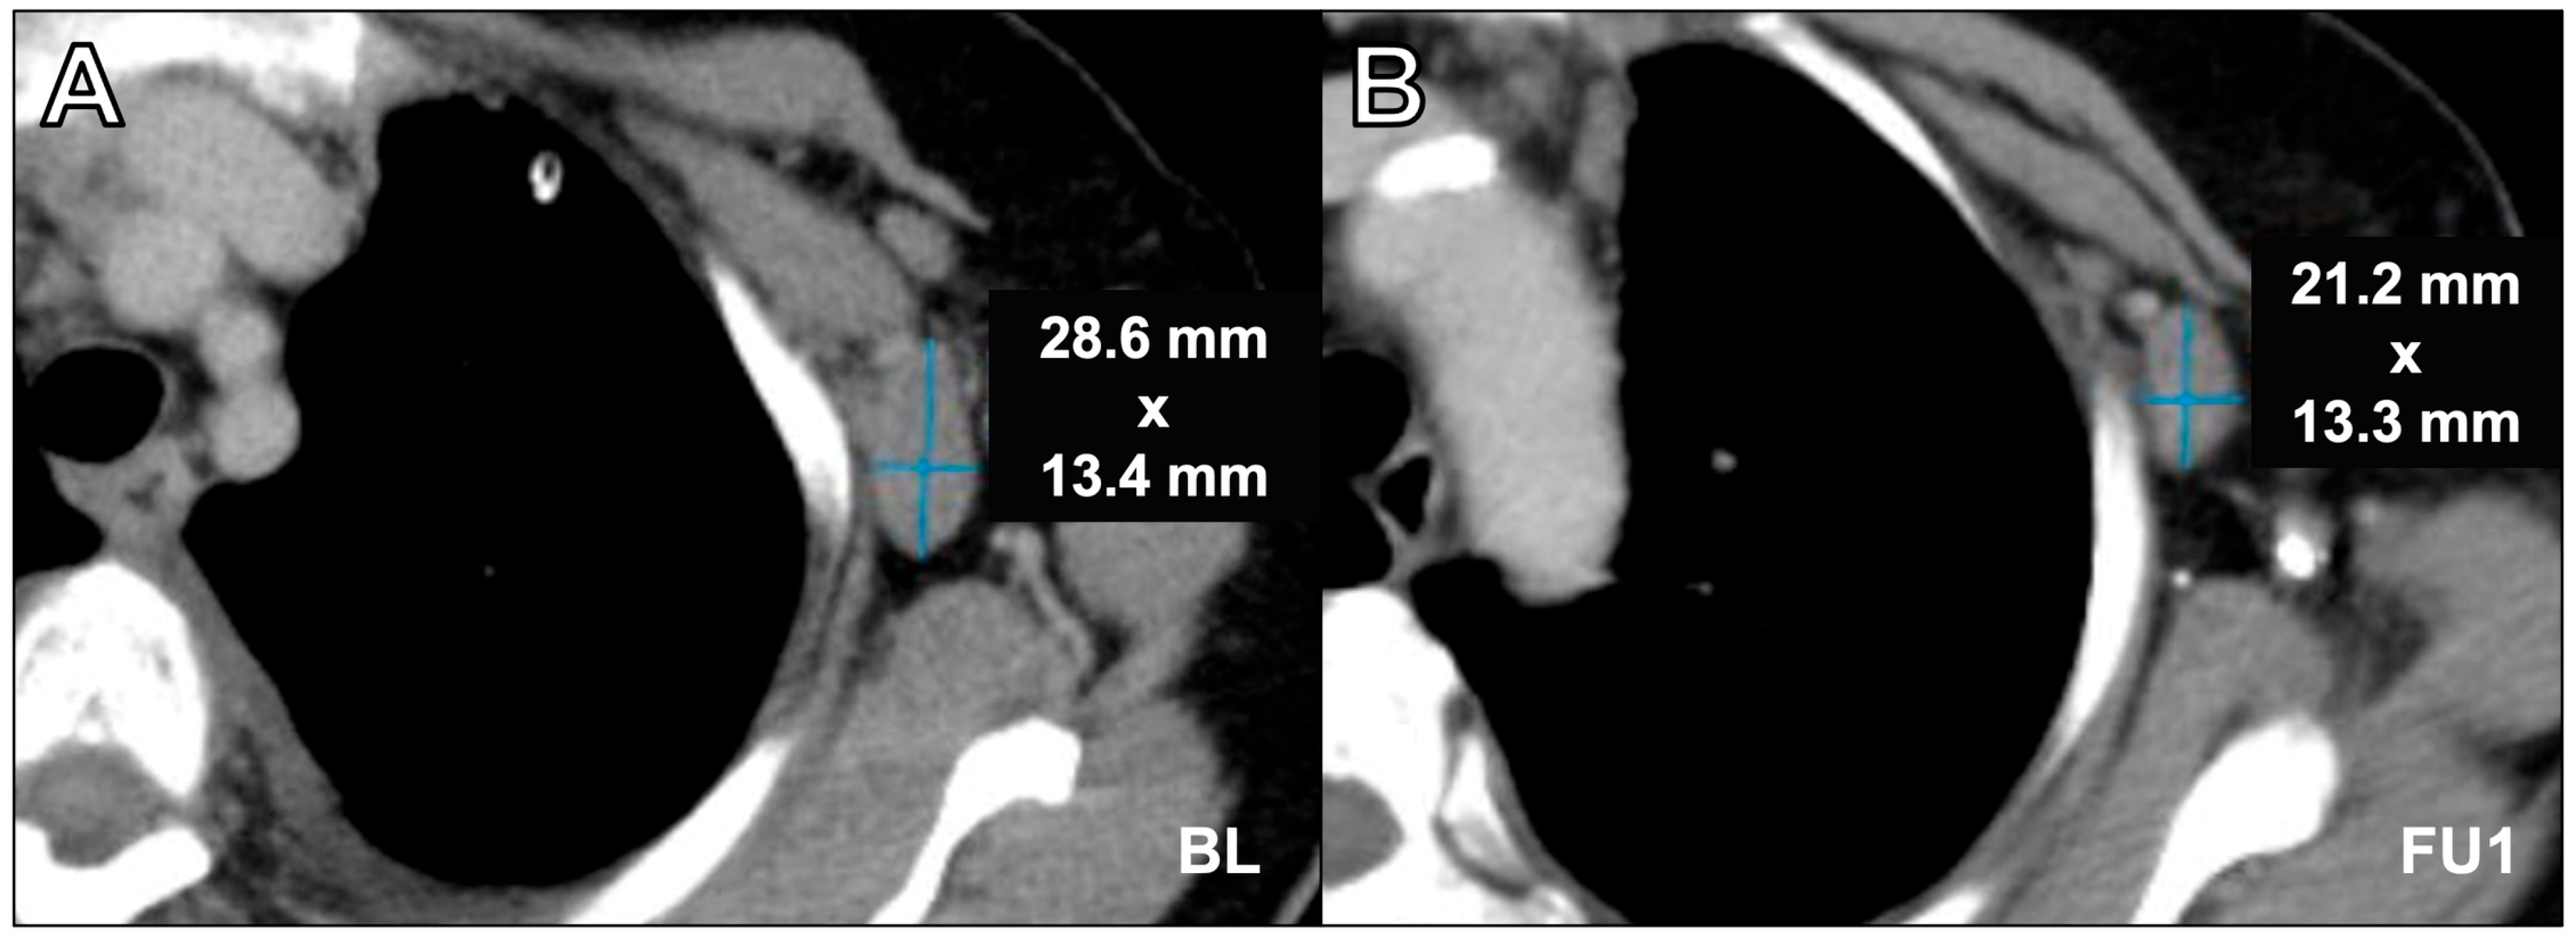

Figure 4.

Axial contrast-enhanced computed tomography scan in portal venous phase in a 76-year-old female with breast cancer and axillary lymph node metastasis assessment at baseline (A) and at follow-up 1 (B). Incorrect lymph node assessment was performed at follow-up 1 by using the long axis. For adequate assessment, it is crucial to measure the lymph nodes in two dimensions, as only the short axis is the relevant value. While the assessment software demands two-dimensional measurements, manual measurement deviating from the short axis is a common source of error. Furthermore, neglecting the longest diameter when it was located on a different plane of the y-axis was an understandable source of error in our study (see the position of the aortic arch in the given example). BL = baseline, FU1 = follow-up 1.